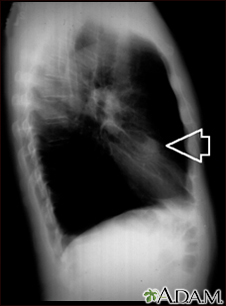

Esta es una radiografía de tórax (RXT) de un nódulo en el pulmón derecho.